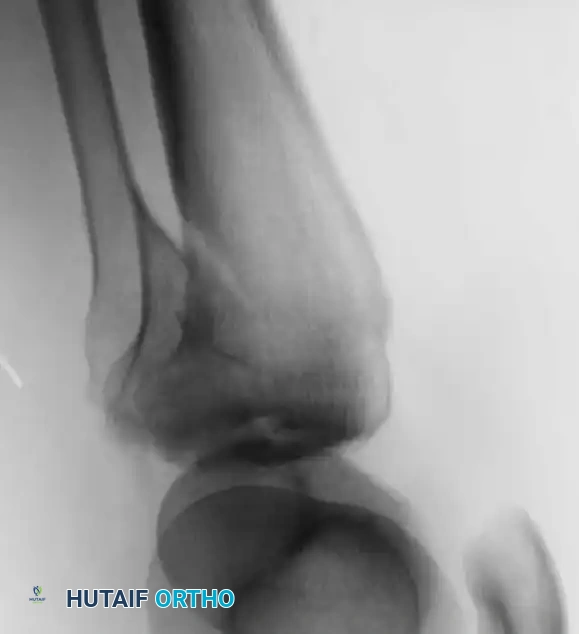

التشخيص الدقيق وتحديد شكل الكسر هو حجر الأساس في التخطيط الناجح للعملية الجراحية. تبدأ الخطوات بصور الأشعة السينية التقليدية لتقييم الوضع المبدئي، ولكنها نادرا ما تكون كافية.

يُعد التصوير المقطعي المحوسب المعيار الذهبي في تشخيص كسور هضبة التيبيا. يوفر هذا الفحص صورا ثلاثية الأبعاد تسمح للجراح برؤية مقدار الانخساف العظمي، وتحديد أماكن الشظايا بدقة متناهية، ورسم خطة للنهج الجراحي الأمثل. كما يمكن الاستعانة بالتصوير بالرنين المغناطيسي لتقييم حالة الأربطة والغضاريف الهلالية التي لا تظهر بوضوح في الأشعة المقطعية.